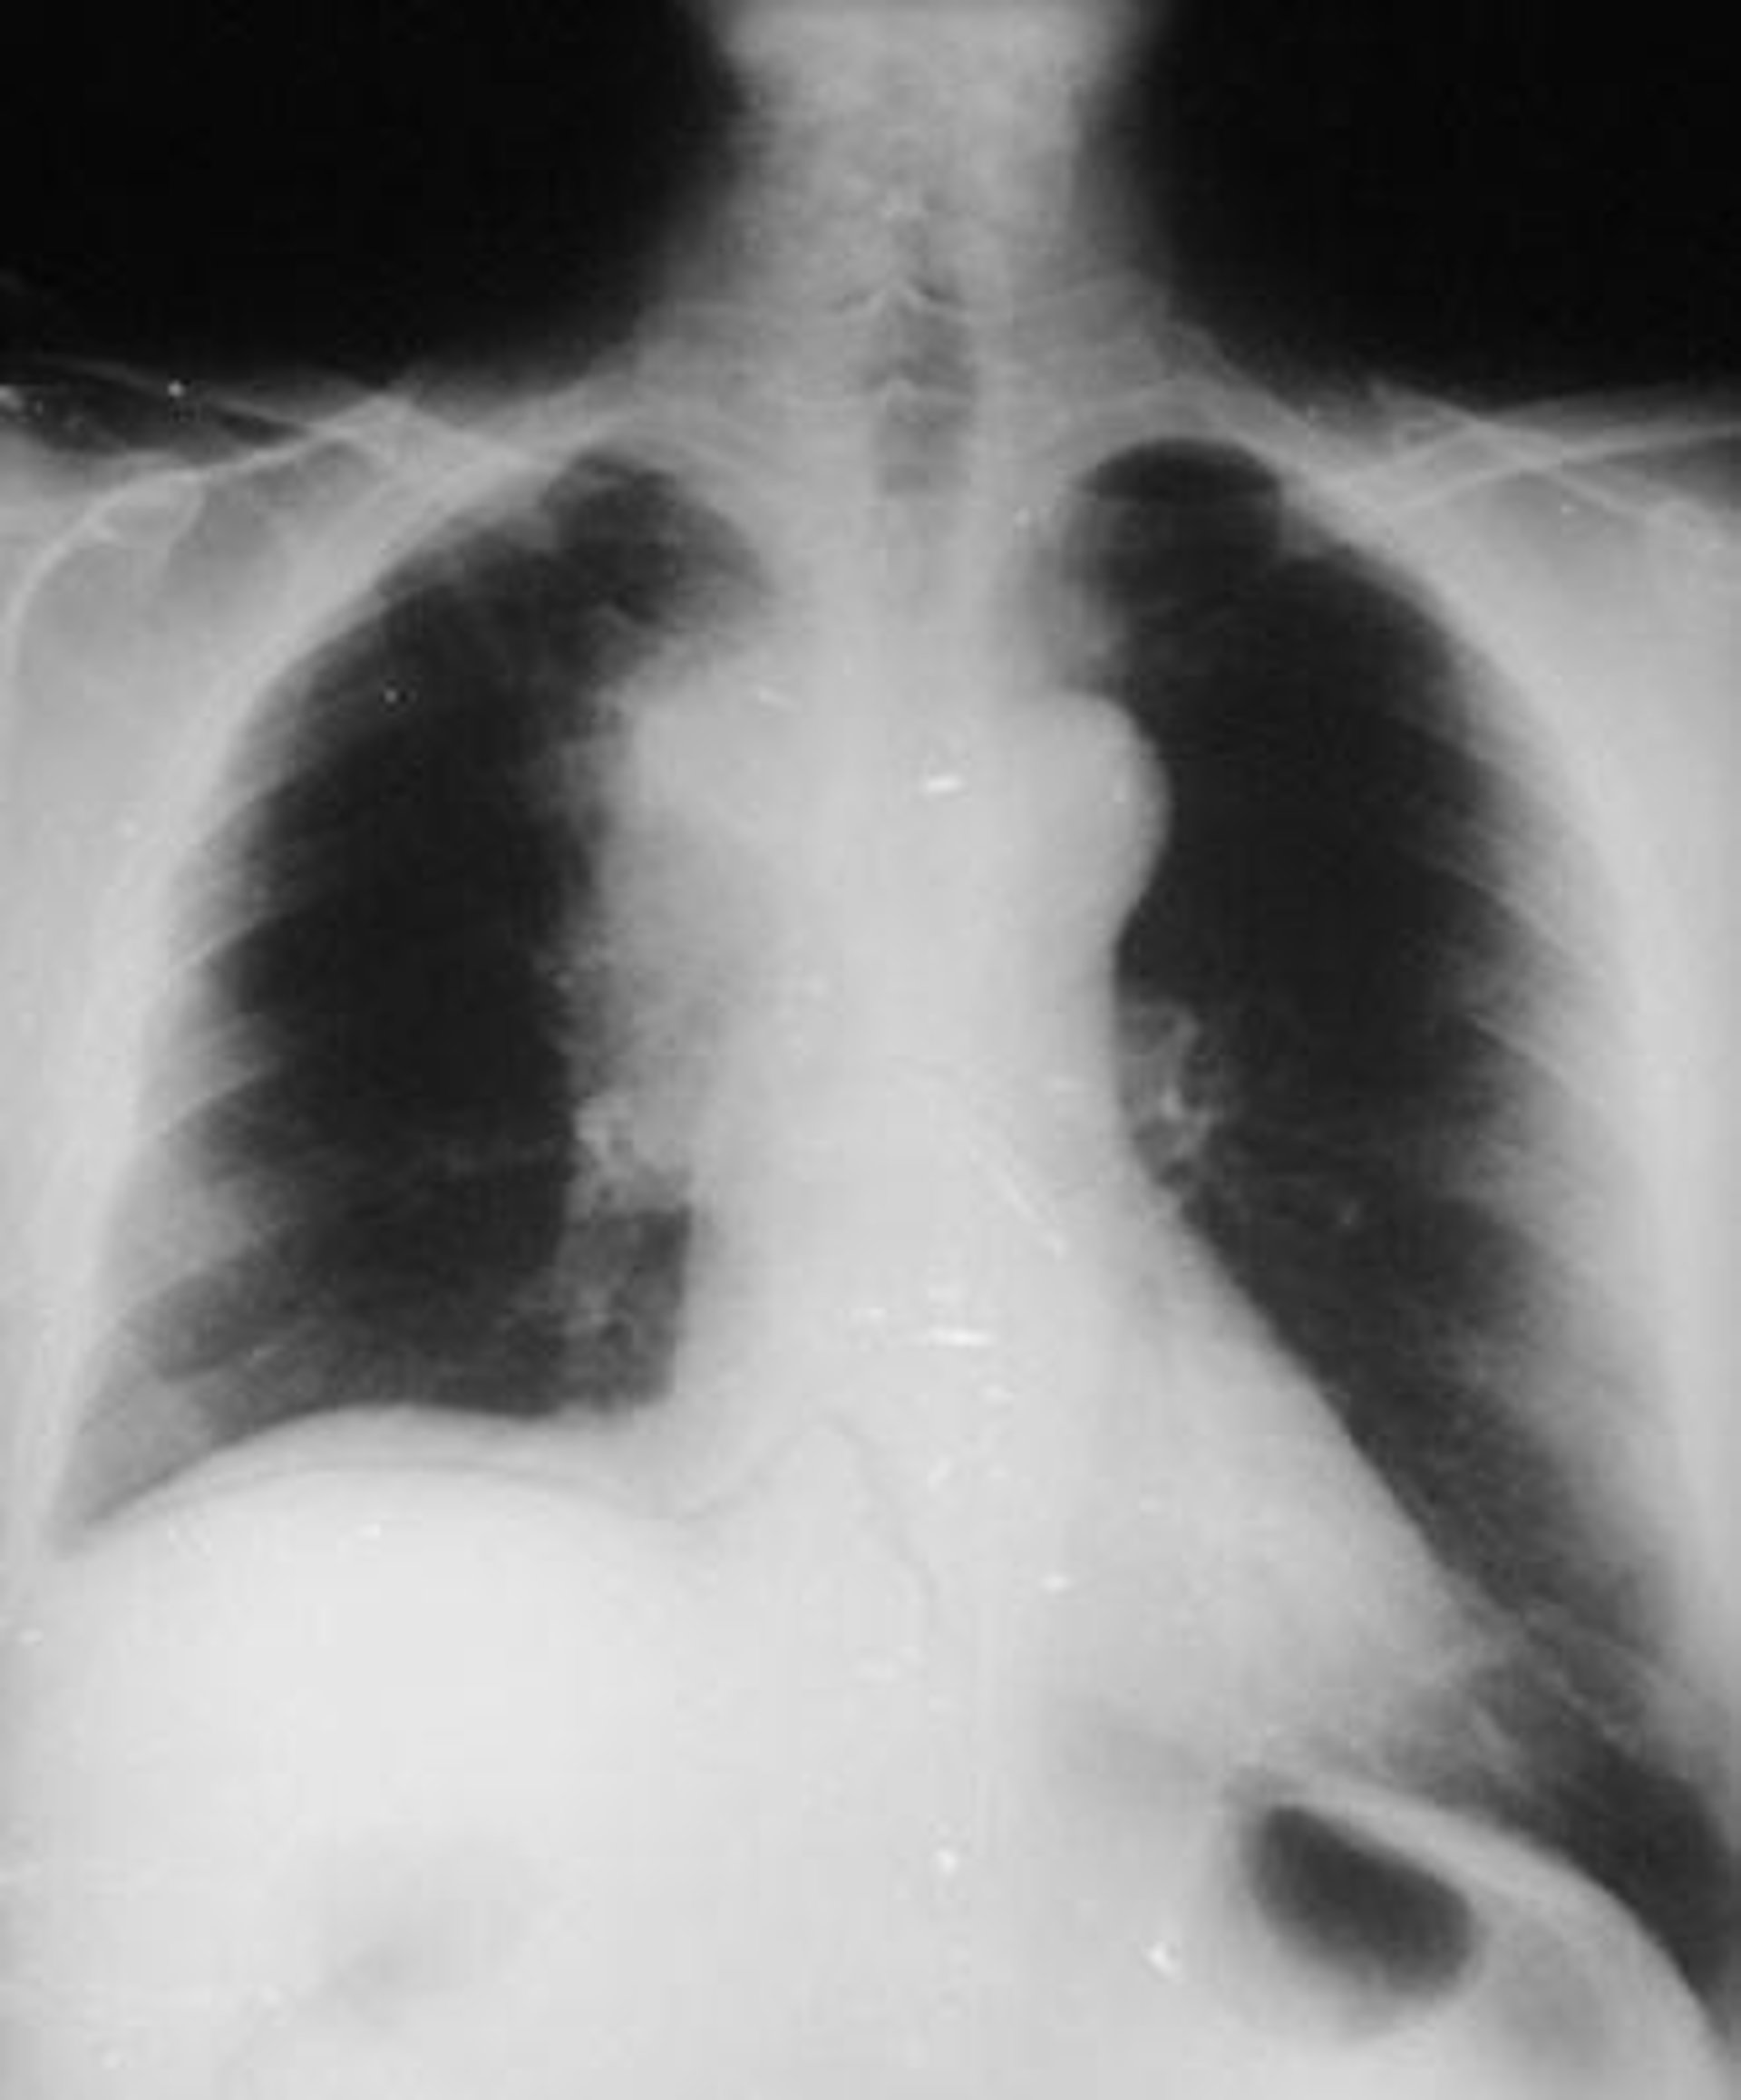

radiografía de pulmón, cáncer

Las medidas de función pulmonar son una vía fiable de evaluar el estado fisiológico de los pulmones y los tractos respiratorios en los humanos. Son también importantes indicadores de la mortalidad, incluso en individuos que nunca han fumado y no tienen problemas respiratorios o éstos son menores.

Dos medidas relevantes del funcionamiento pulmonar son el volumen espiratorio forzado del primer segundo (VEF1), la cantidad de aire que se puede exhalar en el primer segundo, y la tasa de VEF1 y la capacidad vital forzada, la cantidad de aire que puede ser exhalado después de una inspiración completa (VEF1/CVF). La VEF1/CVF se utiliza como un indicador de si existe obstrucción de flujo respiratorio y la VEF1 se emplea para clasificar la gravedad de esta posible obstrucción.